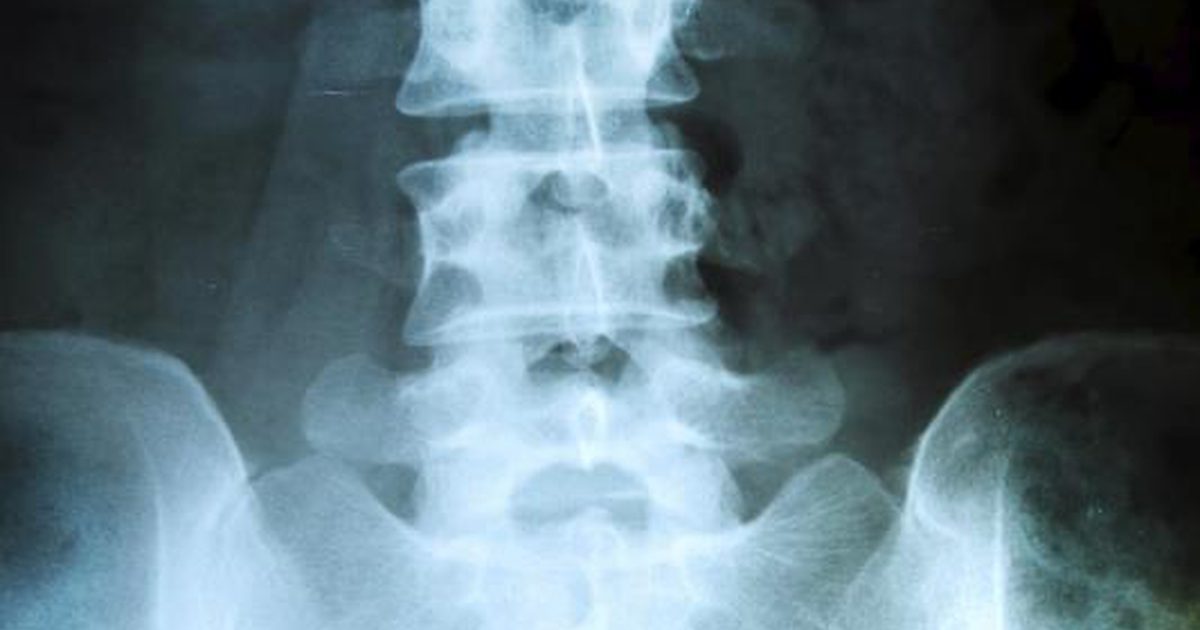

Myelopathy

Myelopathy occurs when the spinal cord is severely compressed, the only treatment for which is decompression surgery. There are multiple causes of myelopathy. In paraneoplastic syndrome, the cause is autoimmune. It's rare for myelopathy to be caused by paraneoplastic reasons, but experts stress the importance of considering a paraneoplastic reason for myelopathy. Patients may present with this condition before they show symptoms of cancer, and identification of the paraneoplastic nature may lead to a cancer diagnosis. Individuals with myelopathy might have pain in their legs, arms, lower back, or neck. They may also experience numbness or weakness. It may be difficult to use fine motor skills for tasks like buttoning a shirt or writing. Walking may also be difficult, and patients may lose their ability to control their bowels.